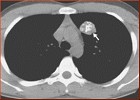

胸部CT检查结论中常出现磨玻璃结节,肺部结节按密度高低分为纯磨玻璃结节、混合磨玻璃结节、实性结节。总体来看,纯磨玻璃结节、混合性磨玻璃结节、实性结节的恶性概率分别约为18%、63%、7%。

1、2为纯磨玻璃结节;3、4、5为混合性磨玻璃结节;6为实性结节